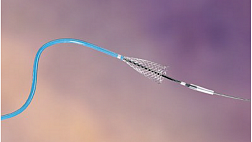

Появление ультратонких гастроскопов с высоким разрешением и технологией NBI (оптического узкоспектрального режима) компания OLYMPUS сделала возможной гастроскопию экспертного уровня под местной анестезией, без наркозных рисков.

Ультратонкие гастроскопы GIF-XP170N и GIF-XP190N с параметром оптики Close Focus, который позволяет приближаться к слизистой на минимальную глубину резкости до 2 мм, обеспечивают качество изображения, сопоставимое с аппаратами экспертного класса.

Эндоскопы проявили себя как удобные и простые в использовании. О надежности можно судить по тому, что при нагрузке более 500 исследований на один аппарат – у них до сих пор нет следов износа.